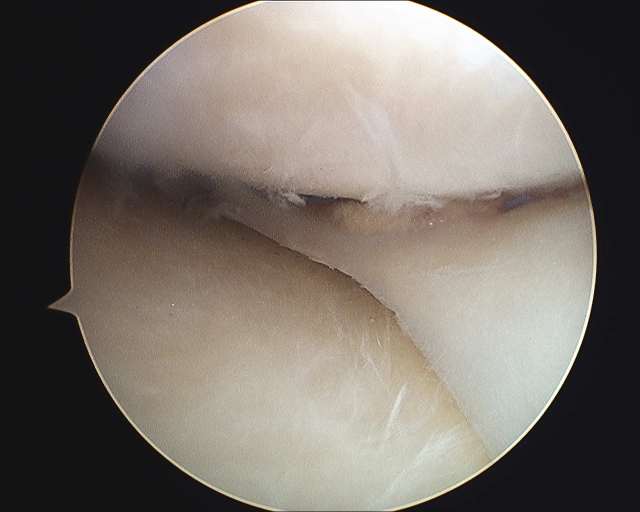

This patient tore his medial meniscus and had a subtotal medial meniscectomy (most of his medial meniscus shock absorber was removed surgically).

A medial meniscus transplantation was performed.